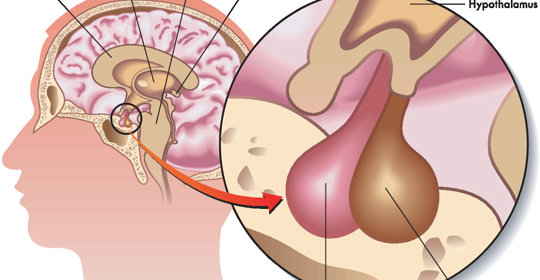

交感神經亢進:作用、失調症狀與治療

交感神經亢進:中樞位置、遞質型別

交感神經亢進:症狀、診斷與治療

交感神經亢進:就診科室與治療方法

交感神經亢進:病因、症狀與治療

交感神經亢進:診斷與治療方法